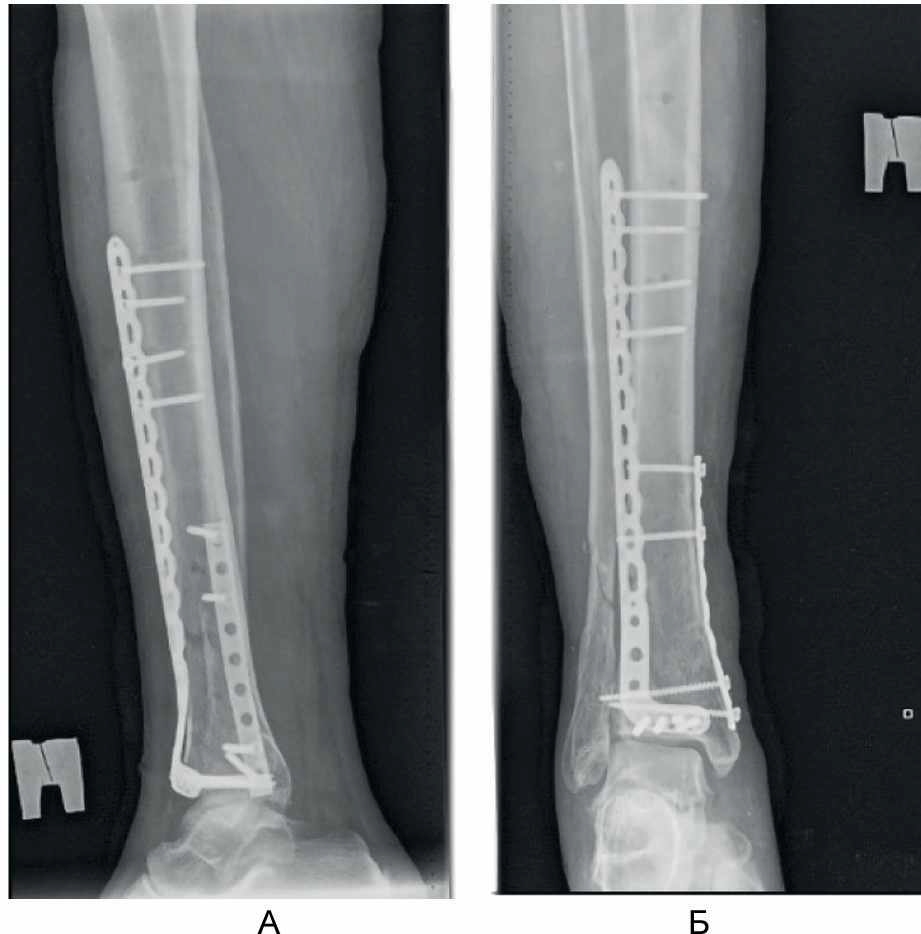

С учетом стабильного состояния пациента, в соответствии с протоколом лечения множественной и сочетанной травмы, пациент доставлен в операционную. Выполнена операция: закрытая репозиция, малоинвазивный остеосинтез левой бедренной кости проксимальным бедренным стержнем, внеочаговый остеосинтез правой голени аппаратом наружной фиксации с умеренной тракцией (рис. 1), первичная хирургическая обработка раны лба.

Рис. 1. Рентгенограммы пациента Б, 66 лет, в день поступления. А – первичная рентгенограмма голени и голеностопного сустава в прямой проекции; Б, В – первичная закрытая репозиция аппаратом наружной фиксации; Г – результат интрамедуллярного остеосинтеза перелома проксимального отдела бедренной кости.